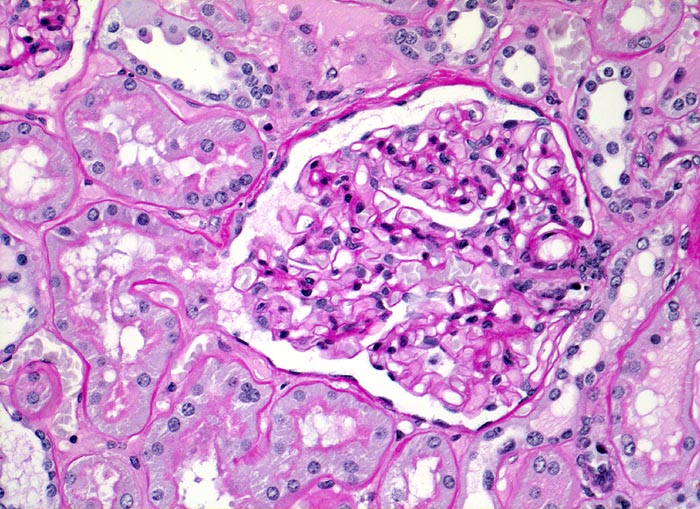

• Verbreiterung des Mesangiums mit Ausbildung von Knoten(noduläre Glomerulosklerose).

• Exsudative Läsionen: Hyaline Schlingenkappen (Proteinthromben in Glomerulumschlingen, im virtuellen Präparat nicht sichtbar) und Kapseltropfen (Proteinablagerungen im Bowman’schen Kapselraum).

• Arteriolosklerose von Vas afferens und efferens (Gefässwandhyalinose durch Ablagerung von Plasmaproteinen und Lipiden in der Gefässwand).

Im allgemeinen ist die Niere infolge von Glomerulumhypertrophie und Tubulushyperplasie vergrössert und derb, die Oberfläche ist granuliert. Bei schwerer Atherosklerose und fortgeschrittener Niereninsuffizienz kann die Niere auch normal gross oder verkleinert sein. Die Kombination von nodulärer Glomerulosklerose, hyalinen Schlingenkappen (=Proteinthromben in den Glomerulumschlingen (> 1916)) oder Kapseltropfen (> 1907) und Arteriolosklerose in Vas afferens und efferens ist beweisend für eine diabetische Nephropathie. Jede einzelne Läsion für sich genommen ist aber unspezifisch. Eine noduläre Glomerulosklerose kann auch vorkommen bei membranoproliferativer Glomerulonephritis (> 2652), Leichtkettenglomerulopathie oder Amyloidose (> 2019). Der nodulären Glomerulosklerose geht bei Diabetikern eine diffuse Glomerulosklerose (> 1906) voraus. Dabei zeigen die glomerulären Basalmembranen und das Mesangium eine progrediente gleichförmige Verbreiterung. Bei der nodulären und diffusen Glomerulosklerose handelt es sich aber wahrscheinlich um zwei pathogenetisch unterschiedliche, sich überlagernde Krankheitsbilder. Typisch bei Diabetikern ist im Unterschied zur arteriellen Hypertonie die Arteriolosklerose von Vas afferens und efferens (> 1911) und oft auch der Vasa recta. Intrarenale Arterien können eine Atherosklerose mit Atheromen zeigen. Subendotheliale Proteinablagerungen teilweise mit Verschluss der Glomerulumschlingen (Schlingenkappen) und knotige Proteinablagerungen in der Bowman'schen Kapselbasalmebran (Kapseltropfen) gehören zu den sogenannten exsudativen Läsionen (> 1919) (> 1920) der diabetischen Nephropathie und führen zu Synechien sowie zur globalen Glomerulosklerose. Gleichzeitig mit den Glomerulumveränderungen treten tubuläre Basalmembranverbreiterungen auf, später eine Tubulusatrophie und interstitielle Fibrose mit Begleitentzündung. Auch die Basalmembranen der peritubulären Kapillaren sind verdickt.